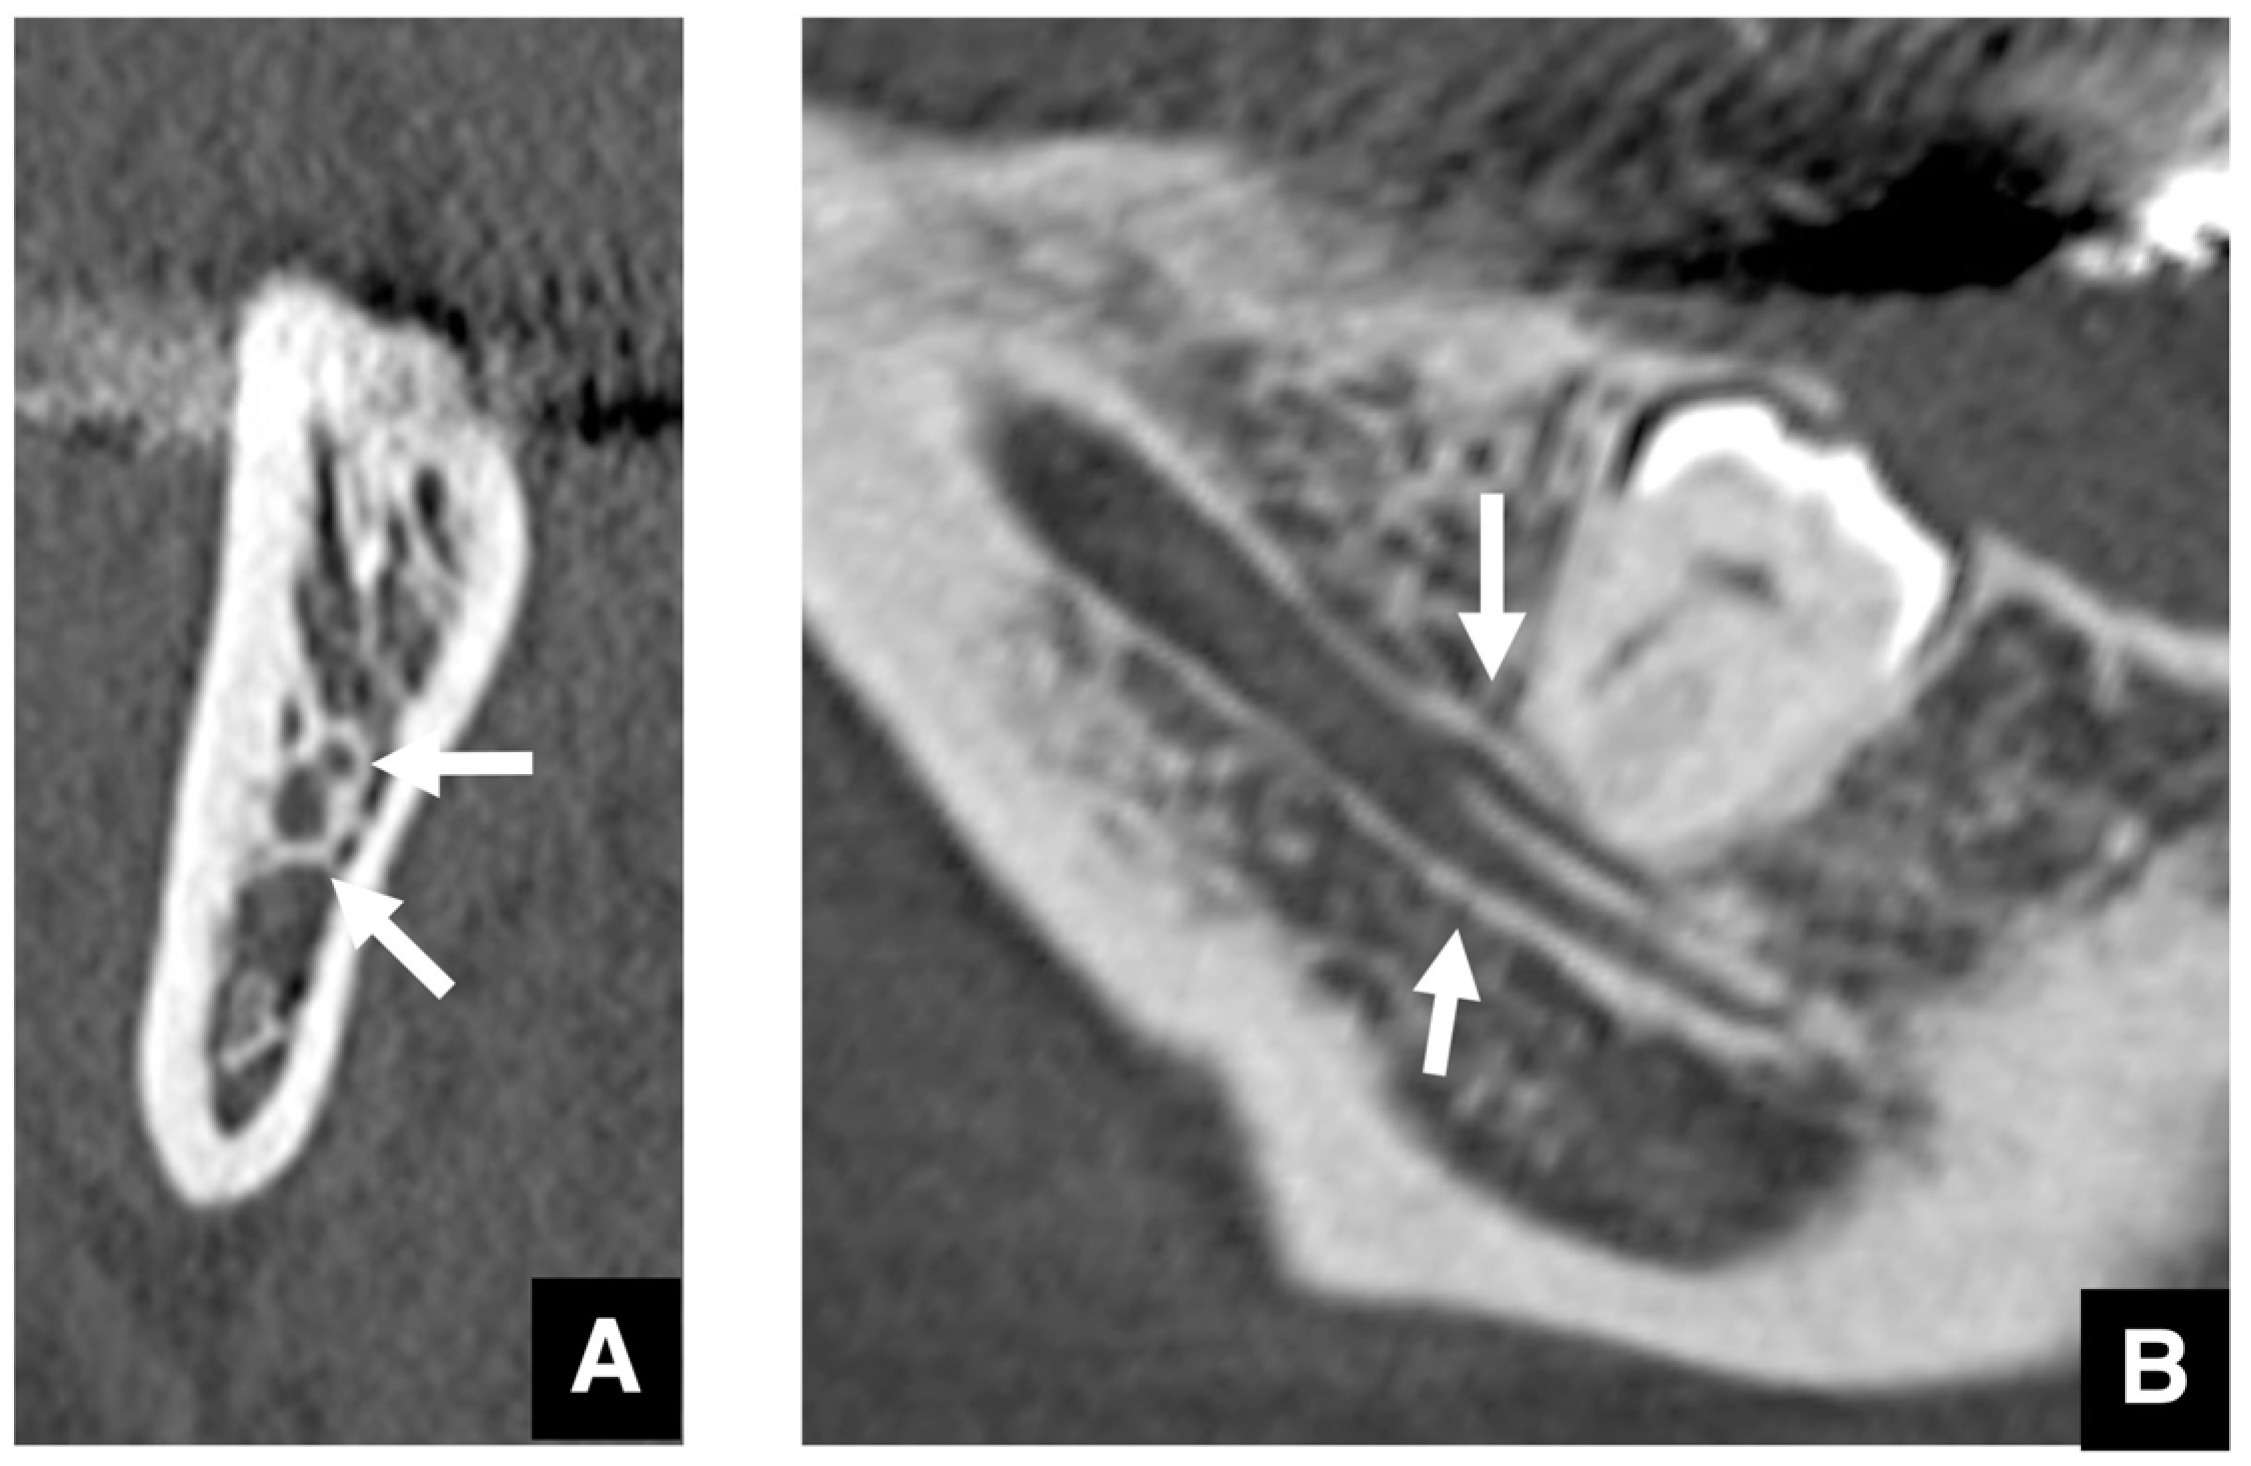

- Yoshioka, I.; Tanaka, T.; Khanal, A.; Habu, M.; Kito, S.; Kodama, M.; Oda, M.; Wakasugi-Sato, N.; Matsumoto-Takeda, S.; Fukai, Y.; et al. Relationship between inferior alveolar nerve canal positions at the mandibular second molar in patients with prognathism and the possible occurrence of neurosensory disturbance after sagittal split ramus osteotomy. J. Oral Maxillofac. Surg. 2010, 68, 3022–3027. [Google Scholar] [CrossRef]

- Yoshioka, I.; Tanaka, T.; Habu, M.; Oda, M.; Kodama, M.; Kito, S.; Seta, Y.; Tominaga, K.; Sakoda, S.; Morimoto, Y. Effect of bone quality and position of the inferior alveolar nerve canal in continuous, long-term, neurosensory disturbance after sagittal split ramus osteotomy. J. Craniomaxillofac. Surg. 2012, 40, 178–183. [Google Scholar] [CrossRef] [PubMed]

- Shah, N.P.; Murtadha, L.; Brown, J. Bifurcation of the inferior dental nerve canal: An anatomical study. Br. J. Oral Maxillofac. Surg. 2018, 56, 267–271. [Google Scholar] [CrossRef] [PubMed]

- von Arx, T.; Bornstein, M.M. The bifid mandibular canal in three-dimensional radiography: Morphologic and quantitative characteristics. Swiss Dent. J. 2021, 131, 10–28. [Google Scholar] [CrossRef]

- Aung, N.M.; Myint, K.K. Bifid mandibular canal: A proportional meta-analysis of computed tomography studies. Int. J. Dent. 2023, 2023, 9939076. [Google Scholar] [CrossRef]

| Setting the osteotomy line 1. Evaluation of the position of the mandibular canal and surrounding bone quality Presence or absence of mandibular canal bifurcation and course of resection site Distance from the buccal wall of the mandibular canal to the buccal cortical bone margin Bone quality around the mandibular canal (CT number) 2. Distance from the mandibular notch to the lingula Whether it is 14 mm or more 3. Morphology of the mandible and variation in cortical bone thickness Cortical bone thickness in the medial osteotomy area and lateral osteotomy area Enhanced safety through improved visibility 1. Medial curvature of the mandibular ramus Mandibular ramus is straight or strong curvature 2. Course of small blood vessels along the bone surface Depression of the buccal-lingual cortical bone from the mandibular fossa to the mandibular ramus region, trabecular bone defect Improved success rates through enhanced postoperative bone integration 1. Degree of interference between bone segments The presence or absence of interference between the proximal and distal bone segments formed during virtual mandibular deformity surgery |